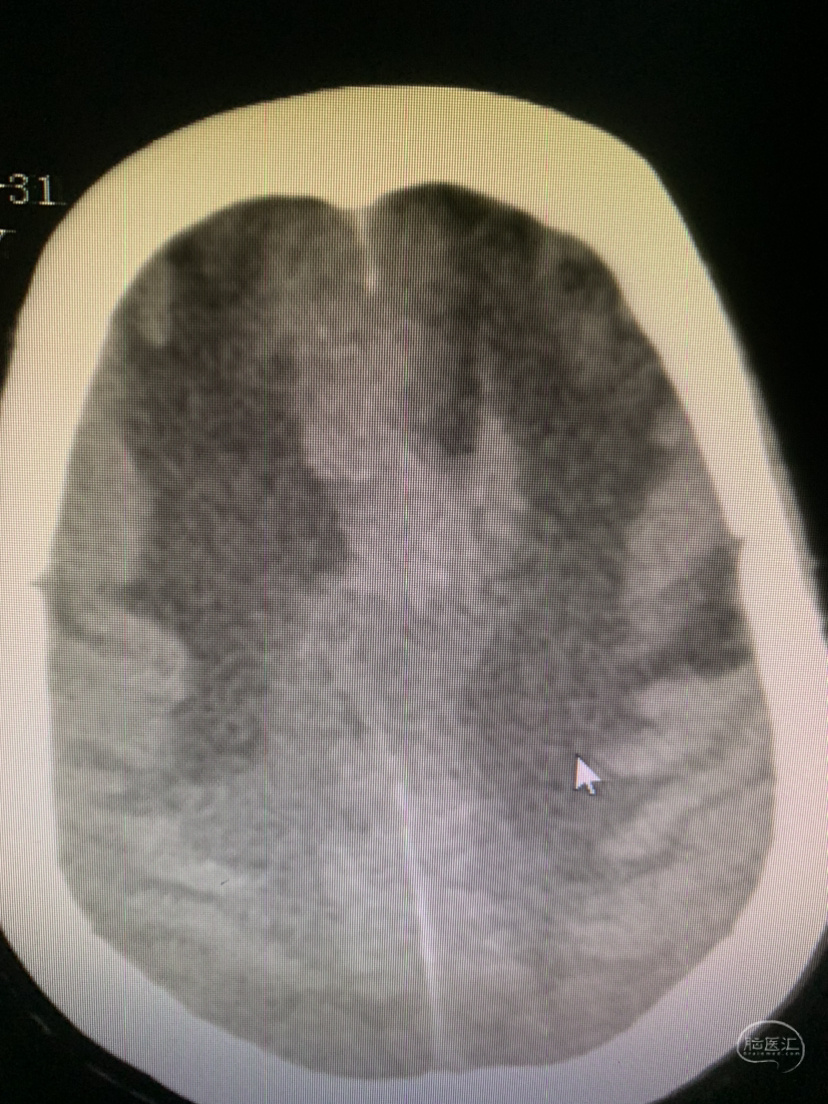

术前CT

术前CT